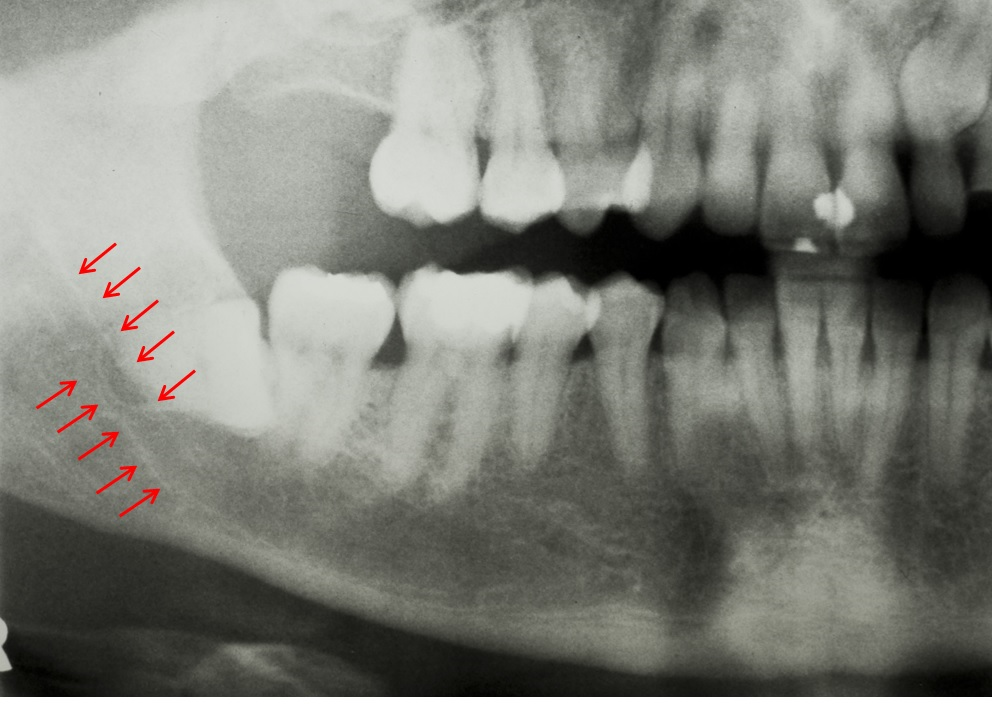

아래 사진에서 빨간 화살표로 표시한 흰 줄이 두 개 보이시죠?

아래턱을 지나가는 터널 같은 구조입니다.

이것을 하악관(Mandibular canal)이라고 합니다.

하악관은 계란껍질 만한 두께를 가진 벽이 있습니다.

이 하악관으로 입술, 아래턱의 피부, 잇몸의 감각을 담당하는 신경(하치조신경, Inferior alveolar nerve)이 지나갑니다.

그리고 치아와 아래턱에 혈액을 공급하는 큰 혈관도 지나가죠.